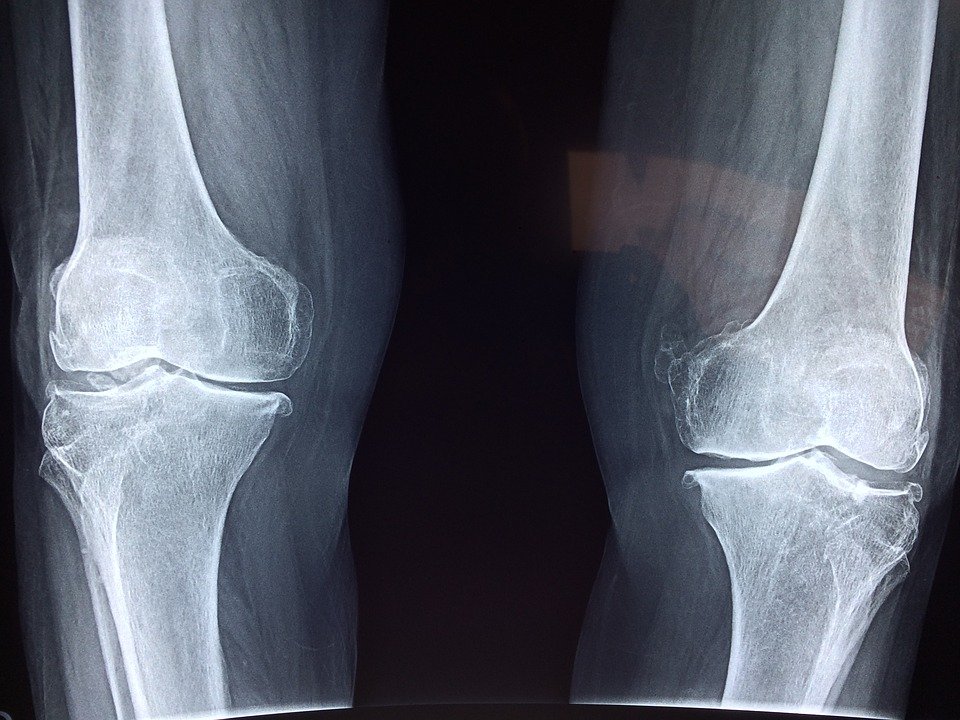

인체는 그야말로 의문 투성이입니다. 그 중에는 명확히 밝혀졌다라고 잘못 알려져 있는 사실도 있는데요, 그 대표적인 예는 인체의 뼈의 개수입니다. 인간의 뼈의 개수는 몇 개일까요? 인터넷에 검색해보면 뼈의 개수는 206개라고 하는데, 사실 이건 정확한 숫자는 아닙니다. 왜냐하면 인간의 뼈는 평생에 걸쳐 계속해서 결합되며, 나이를 먹으면 먹을 수록 뼈의 총 개수는 줄어들기 때문입니다.

뼈의 발육은 태아 때부터 시작됩니다. 먼저 전체적인 골격이 형성되고, 그 다음부터는 뼈로 성장하게 되는 세포인 조골세포(osteoblast)가 골화중심이라고 불리우는 클러스터에 모여 뼈가 형성되기 시작하는 것이죠. 임신 후기인 제3기 초엽 쯤에는 태아의 몸에는 이러한 클러스터가 약 800개 가량 발생합니다. 즉, 태아 상태일 때의 인간에게는 매우 작은 뼈가 800개 있다고 볼 수 있으며, 태어날 때 쯤에는 이 뼈들이 결합하여 결국 300개 정도가 됩니다.

그리고 출생 이후부터는 독립된 상태였던 300개의 뼈들도 차례대로 결합하면서 그 수가 점점 줄어들게 되는 것이죠. 과거에는 이러한 뼈 결합은 유아기 때만 발생한다고 알려져 있었으나, 최근 연구 결과로는 연령을 불문하고 지속된다는 것이 밝혀졌습니다. 이런 점 때문에 기계를 동원해 인체를 스캔이라도 하지 않는 한, 인간은 자신의 몸에 정확히 몇개의 뼈가 있는지 알 수 없습니다. 또 뼈의 개수 뿐만 아니라 성인의 경우에는 나이를 먹을 수록 골밀도도 감소합니다. 뼈의 총중량은 20대를 기점으로 최고치에 도달합니다만, 그 이후의 골밀도는 계속적으로 하강하고 말죠.

정리하자면, 태아 상태일 때 인간은 최대 800개의 뼈를 가지고 있었습니다. 그러나 이 작은 뼈들이 서로 결합하여, 출생 시점에서는 약 300개까지 줄어들게 되죠. 이 뼈의 결합은 유아기 뿐만 아니라 인생 전반에 걸쳐 계속해서 진행되며, 이 때문에 검사를 해보지 않는 이상 인체에 뼈가 몇 개 있는지는 알수 없는 것이죠. 세간에 알려져 있는 206이라는 숫자는 사실 어디까지나 성인 평균 뼈의 개수였던 것입니다.